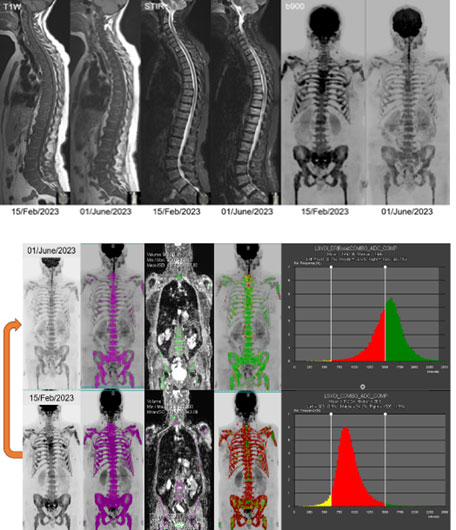

WB-DWI is also a powerful tool for monitoring treatment effectiveness, as changes in cellularity and water content often precede changes visible on conventional imaging (Figure 3a). Combining DW-MRI information with fat and bone images allows the spatial mapping of tumor cell killing and host tissue responses, including inflammation, healing, and repair.

Figure 3: 68F. Metastatic breast cancer with bone, node, and liver disease. Reassessment after three cycles of cyclin-dependent kinase 4 and 6 (CDK4/6) inhibitors. Figure 03A (top): The morphological T1-weighted and STIR images are not clear regarding any therapy response, but there is a decrease in the bone marrow signal on the b900 MIP images. Figure 03B (bottom): The bottom row is before treatment, and the top row is after therapy for the dates indicated. The whole skeleton was segmented using thresholding, and a mask was applied to the ADC maps. Corresponding ADC histograms show a good response by an increase in mean ADC from a median of 881 to 1505 (µm^2/s).

Quantitative image analysis is a crucial feature, enabling the assessment of multiple or all lesions in the body as volumes of interest (Figure 3b). Tools like histograms can evaluate the spatial distribution of ADC values within tumors, capturing heterogeneity of responses. The functional diffusion map or ADC parametric response map technique can also measure spatial changes in ADC, enabling radiomic analyses. However, their use may be limited by physiological motion or tumor distortions. For bone marrow response, WB-DWI is effective in monitoring therapy evaluation because of the fixed nature of the skeleton. Successful chemotherapy for primary bone tumors such as osteosarcomas is linked to higher tumor ADCs after treatment. In multiple myeloma, an increase in ADC values during treatment correlates with a good response. While morphological MRI may reveal persistent viable lesions after treatment, combining it with diffusion-weighted imaging enhances diagnostic accuracy for objective response, aligning more closely with clinical benefit.